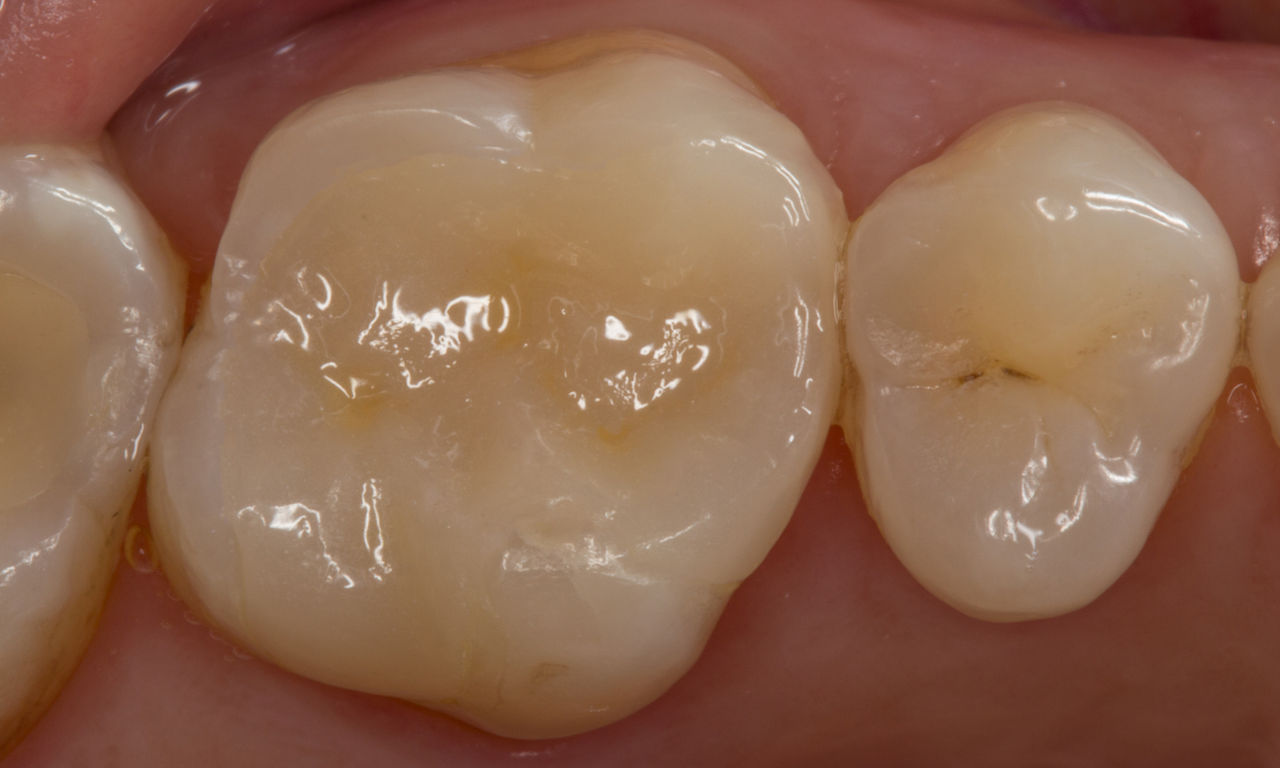

Before: Failed amalgam restoration needing replacement. Patient complaining of sensitivity and tooth presenting multiple cracks.

After: Chairside CAD/CAM partial crown restoration fabricated with CEREC Tessera Advanced Lithium-Disilicate glass ceramic.